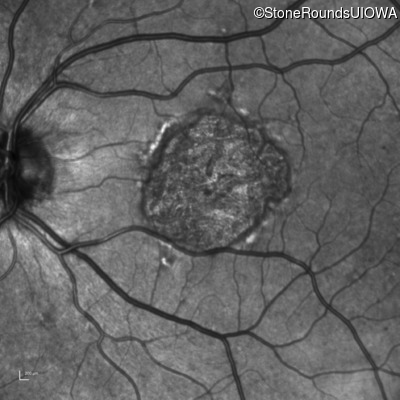

Pattern Dystrophy (IIC)

Age at visit: 51 years

This 51 year old woman first noticed some metamorphopsia in her left eye in her early 30's.

Pattern Dystrophy PRPH2 IVS2+3 A>T   AD